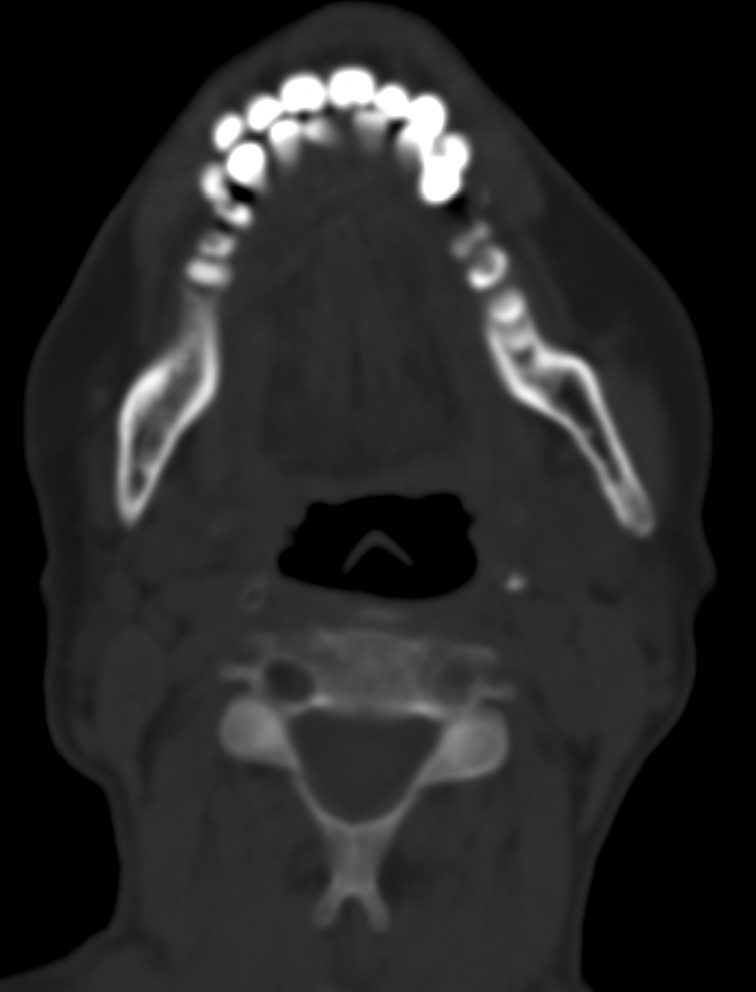

女,68岁。发现上唇无痛性肿块2年多,查体局部皮肤隆起,其余未见异常。

病灶ct值约42hu。

病理结果:唾液腺混合瘤。